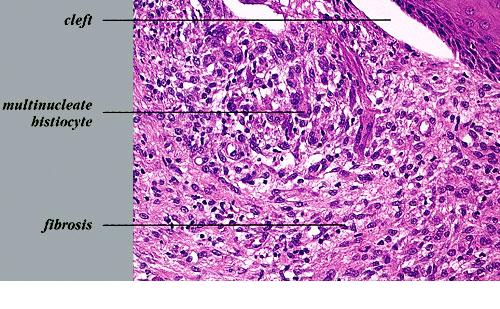

Atlas of skin histopathology

Acne vulgaris erythematous papule =العد الشائع